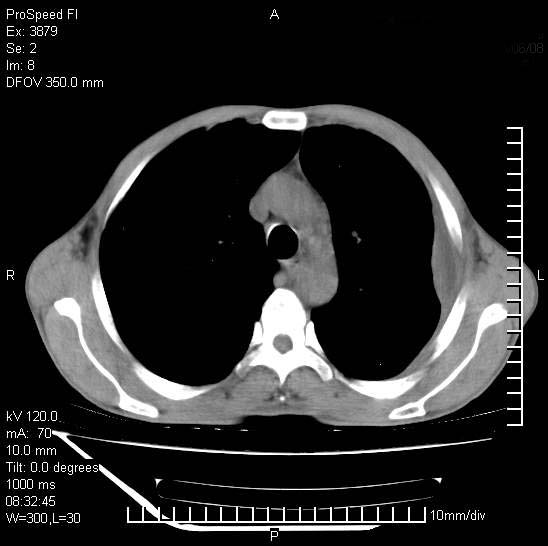

以下是引用37度在2008-6-6 11:20:00的发言:[br]1.包裹性积液,多考虑结核性;[br]2.穿刺术后改变。

以下是引用312nanyang在2008-6-6 15:12:00的发言:[br]基本支持楼主意见[br]疑问?左下肺支气管旁的软组织(16层)密度怎么解释?淋巴结还是斜裂胸膜增厚所致?能否增强进一步检查